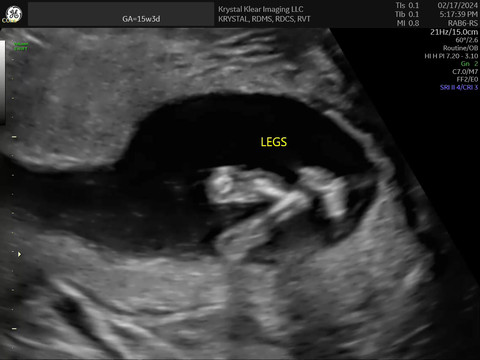

click to view- 15 weeks